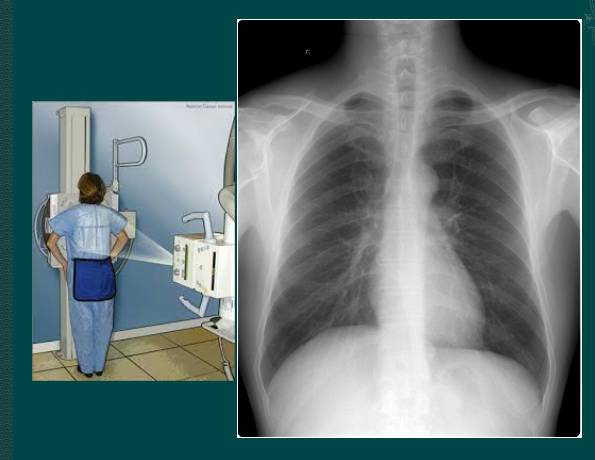

1.胸部正位片

临床拍标准的胸部正位片其实是后前位片,如上图。

上图为正常胸部后前位片